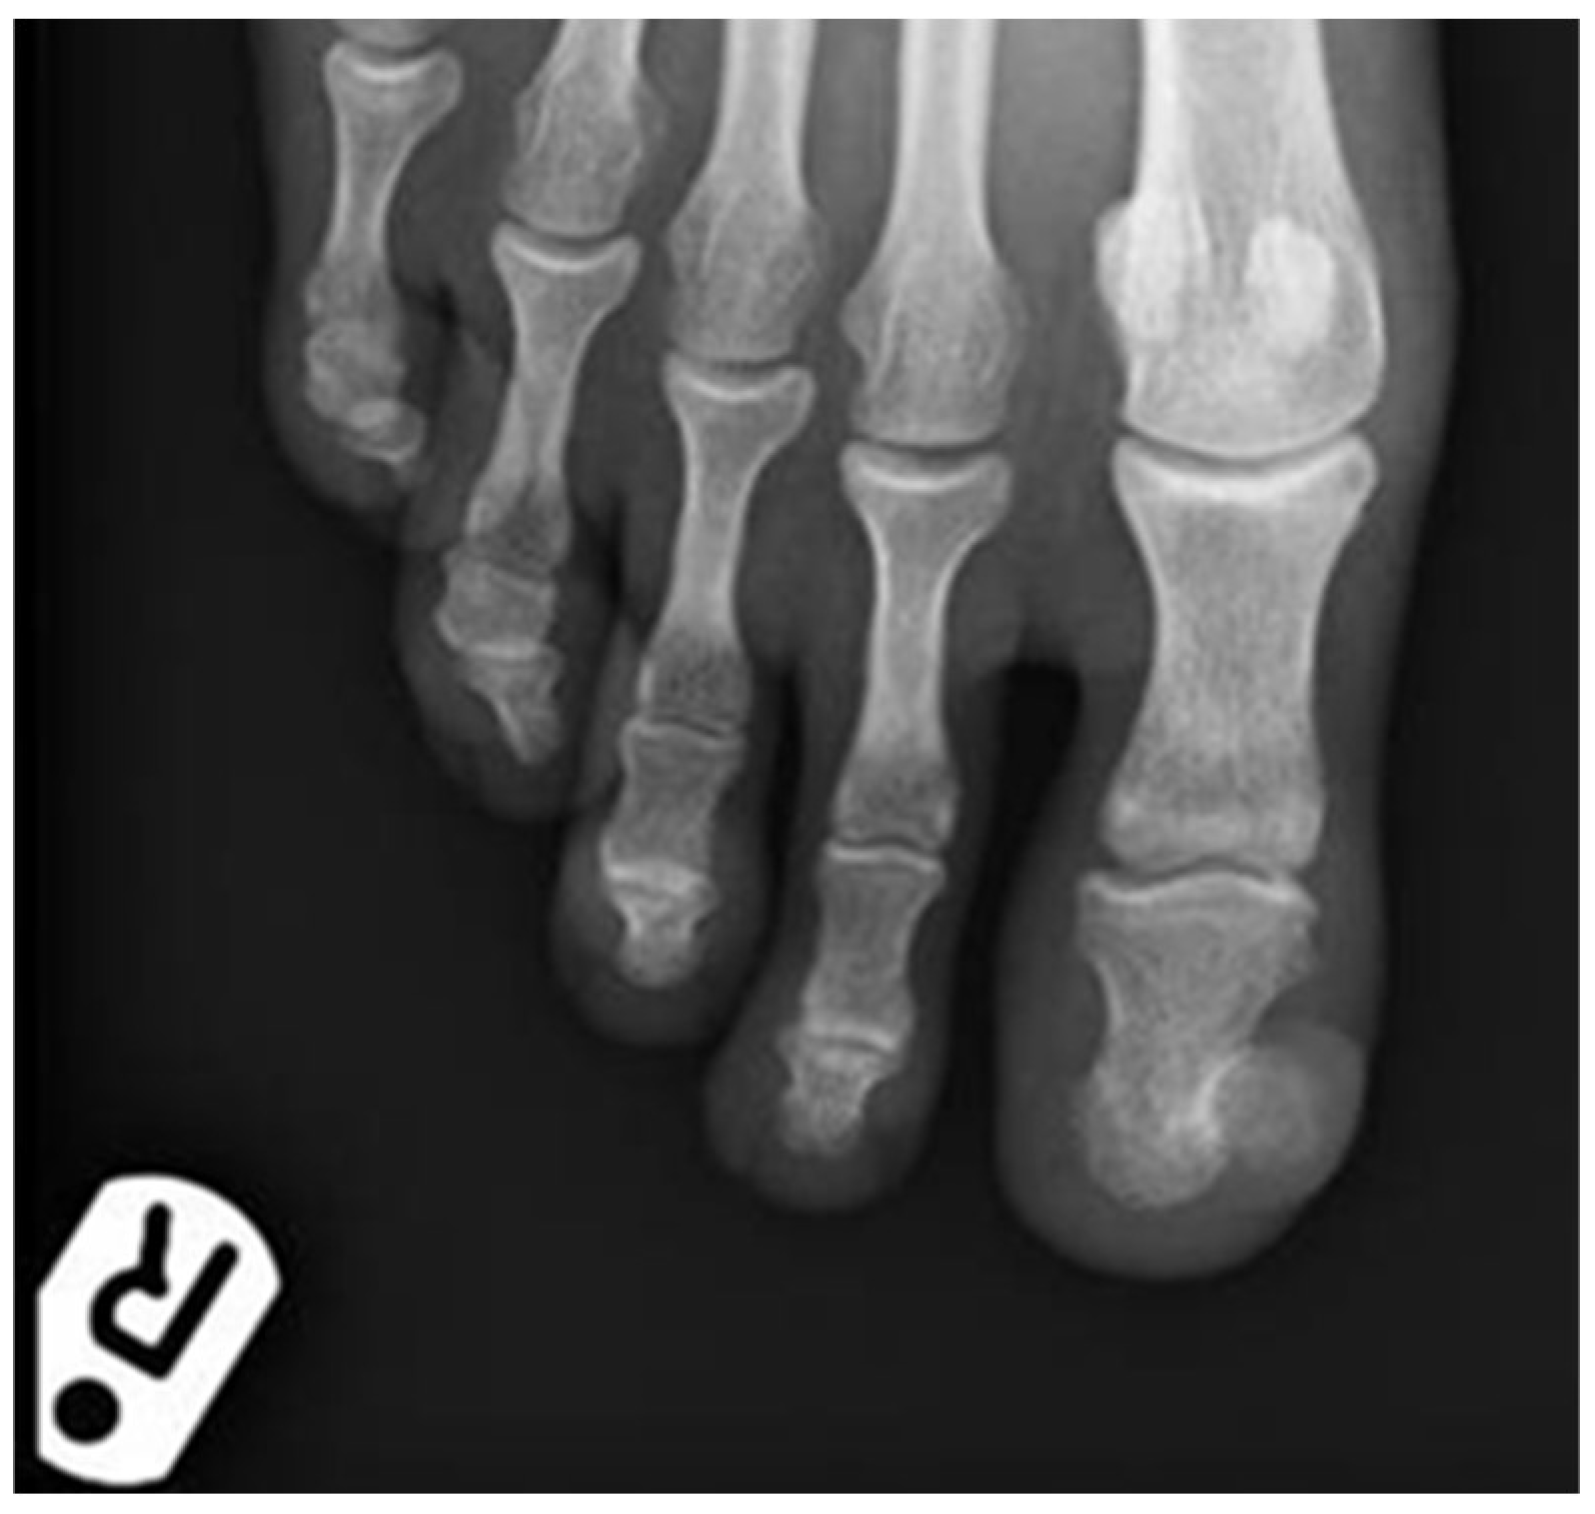

It measured approximately 20 × 20 mm. At this stage a SE was suspected, and a plain X-ray showed a significant exostosis arising from the distal phalanx of the toe (Figure 2). The lesion was shaved and sent for histology and a second specimen was taken from the bone at the deep margin of the lesion. The histology showed a reactive myofibroblastic proliferation with a myxoid stroma and focal areas of keloidal-like collagen overlying mature cartilage and bone fully in keeping with a SE (Figure 3A–D). The deep specimen showed fragments of mature bone. Immunohistochemistry confirmed the myofibroblastic phenotype overlying the SE with the majority of spindle cells showing strong and diffuse smooth muscle actin (SMA) positivity (Figure 3E). There was also so called “tram-track” morphology to the SMA staining pattern which is very suggestive of myofibroblasts (Figure 3F). The spindle cells were negative for AE1/3, MNF116, S100, CD34, p63, and desmin. The exostosis was fully removed in July 2019 and the defect was covered with a full-thickness skin graft from the right groin. The post-operative period was uneventful and follow-up showed good donor and graft site healing and no signs of recurrence. Histology of the final surgery showed an ulcerative SE with fibrous granulation tissue representing reactive changes to the previous surgical intervention.

Figure 2. Antero-posterior plain radiograph of the right forefoot showing exostosis arising from the distal phalanx of the right big toe.